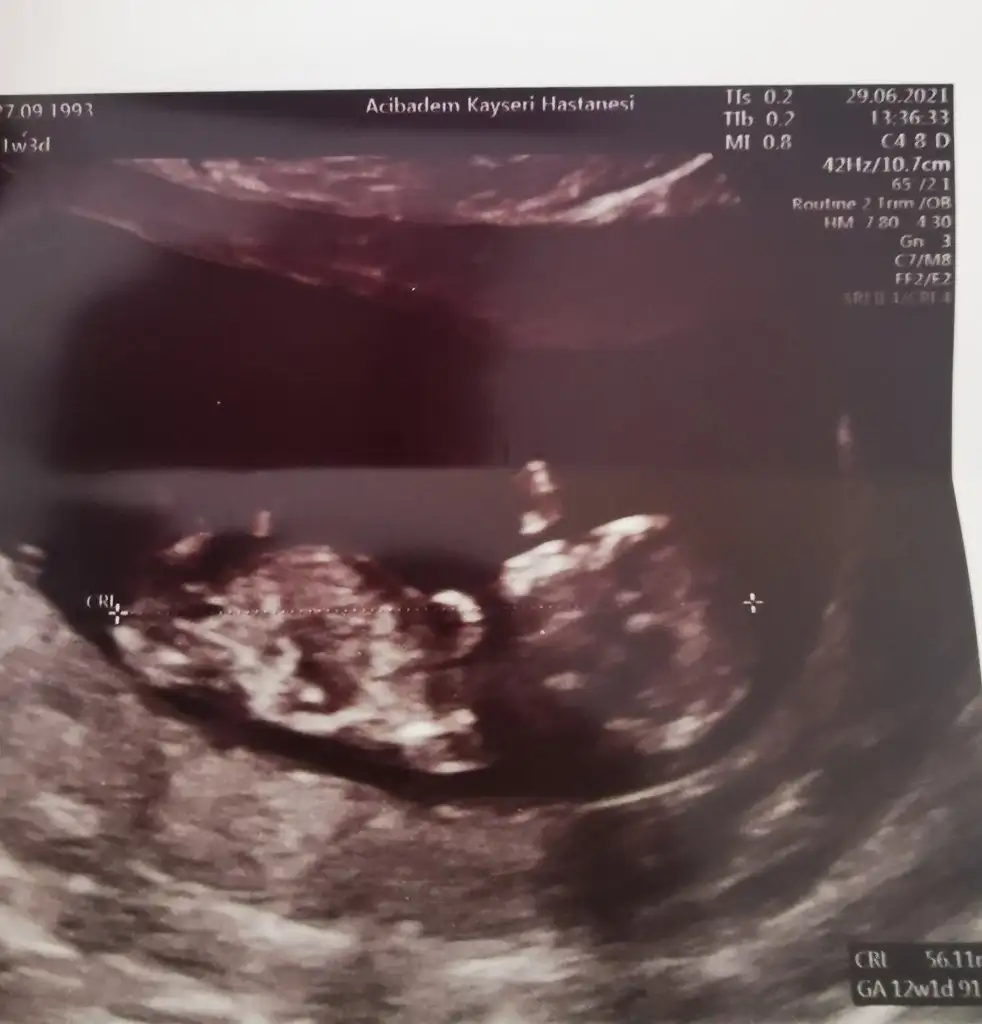

Burada 9+4 üz tahmin alabilir miyiz karından ultrason merak işte teşekkürler şimdidenErkek görünüyor![]()

Çok erken en iyi 11 12 13 haftalar olmalı şimdilik kız yönünde ama yanıltabilirBurada 9+4 üz tahmin alabilir miyiz karından ultrason merak işte teşekkürler şimdidenEki Görüntüle 2894467